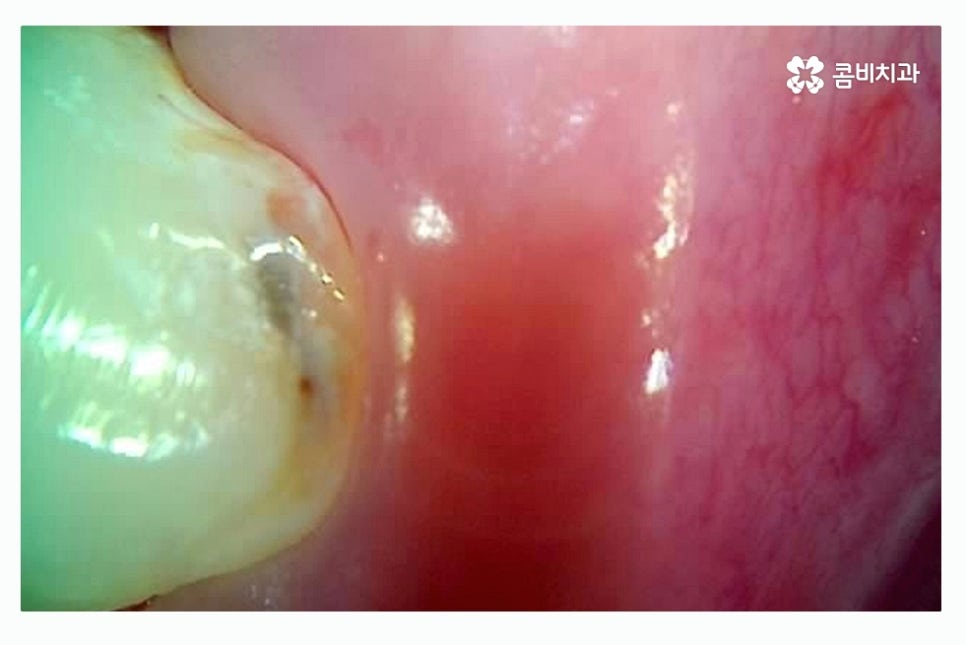

충치의 대표적인 증상은 시림, 통증, 구취가 대표적이지만

충치 초기에는 별다른 증상이 없이 까만 점으로 나타나는 경우가 많으며

치아 사이 혹은 내부의 경우에는 눈으로 확인도 어려울뿐더러

증상으로 충치를 느끼는 시점에서는 이미 충치가 상당히 진행된 경우가

많기 때문에 주기적인 검진을 통해서 초기 발견과 치료를 하는 것이 중요하다고 볼 수 있어요.